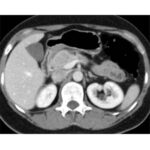

Tomografía de abdomen con cte ev: del 20/10/2023.

Complicaciones posquirúrgicas

Ahora bien, como se mencionaba al principio, el estudio ecográfico es de muy baja sensibilidad y se identifique o no la lesión por este estudio, nuestro siguiente paso en el algoritmo diagnóstico de esta lesión es la tomografía. Esta es la prueba no invasiva inicial, con una sensibilidad del 63% al 83%, y detecta del 70% al 80% de los tumores. Esta debe realizarse como un estudio trifásico: fase arterial temprana a los 30 segundos, fase venosa a los 70 segundos, fase tardía de 3 a 5 minutos. La característica de estos tumores por tomografía es que se presentan como una masa sólida que tiene un ávido realce en la fase arterial, cuyo realce se mantiene y se observa más tenue en la fase venosa y en los tiempos tardíos la lesión se homogeniza.

Para mi caso, y dando una visión general de los métodos de imagen no invasivos en esta revisión retrospectiva, solo a uno de los pacientes se le detectó la lesión por ecografía, donde se visualizó una lesión nodular hipoecogénica en el cuerpo del páncreas. A los demás pacientes se les detectó la lesión por tomografía en estudio trifásico, donde resaltan las características ya descritas por la literatura de lesiones hipervasculares con intenso realce en fase arterial, localizadas en diferentes partes del páncreas, como cabeza, cuerpo y cola.